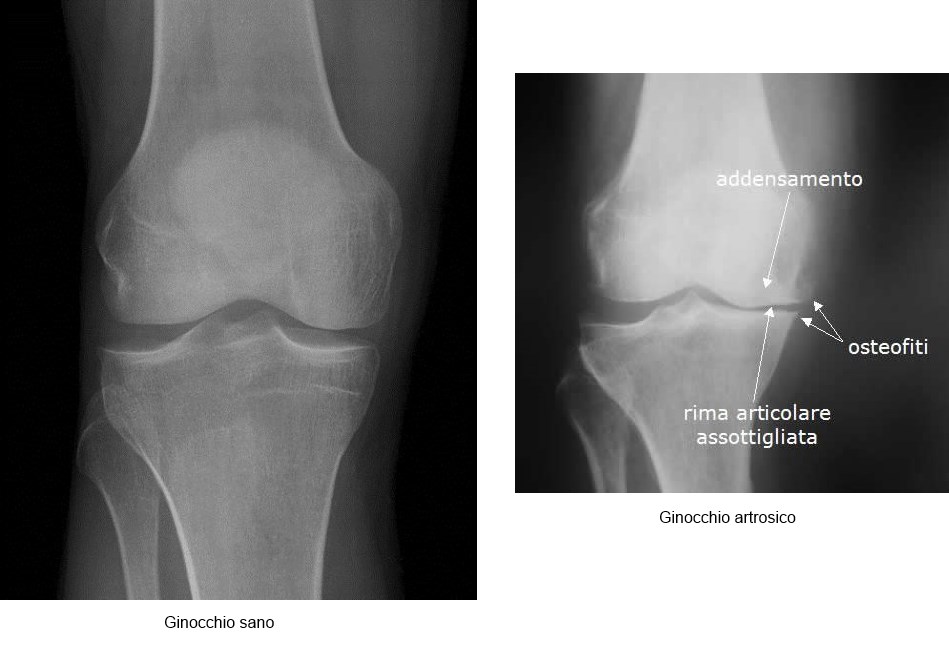

L’artrosi del ginocchio, o gonartrosi, è la malattia cronico-degenerativa del ginocchio più comune in età senile.

Questa patologia comporta un danno articolare crescente, fino a compromettere notevolmente la funzionalità dell’articolazione.

La gonartrosi caratterizzata dalla degradazione del patrimonio cartilagineo fino a interessamento progressivo dell’osso subcondrale ma è una patologia anche dei legamenti, della capsula articolare, della membrane sinoviale e dei mm periarticolari.